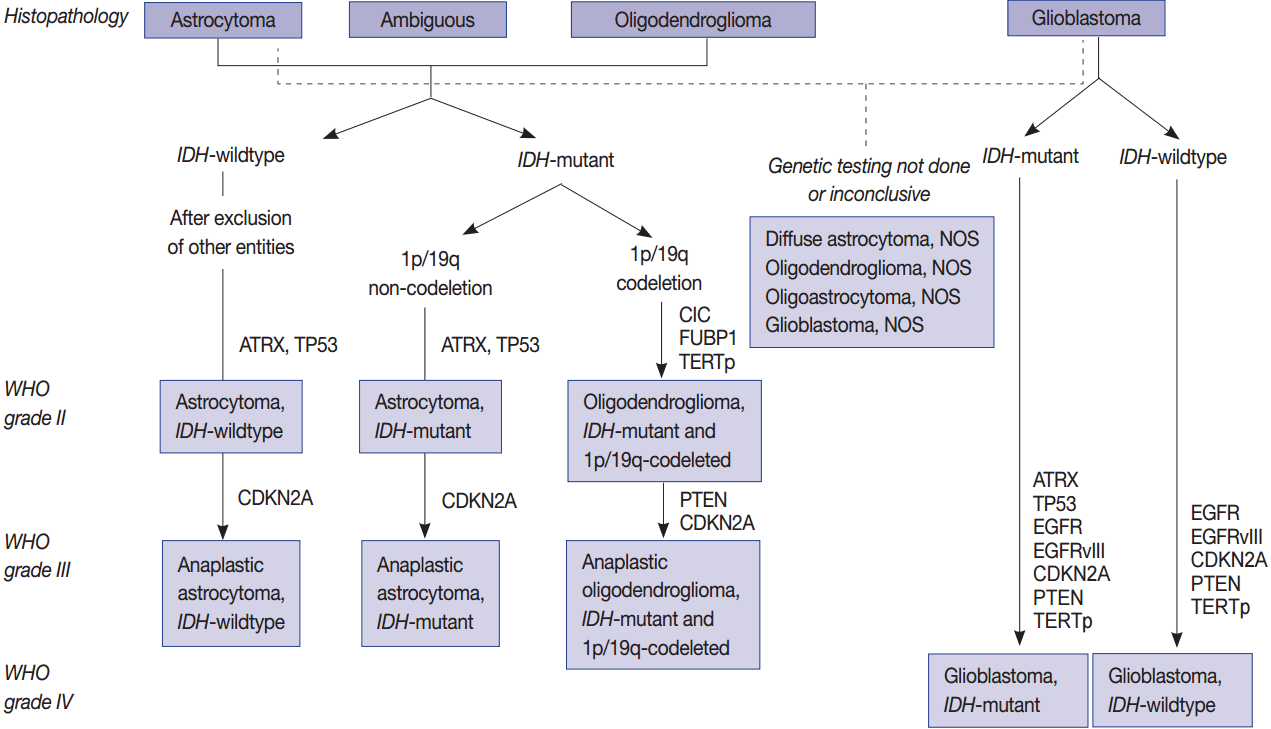

Grades WHO

Marqueurs Importants

- IDH muté : Meilleur pronostic

- 1p/19q co-déletion: Meilleur pronostic et réponse à la Cx (pertmet d’identifier l’oligodendrogliome)

- MGMT : Meilleure réponse au témozolomide (chimio), meilleur survie

Grade II

Oligodendrogliome (grade II)

- Comme un astrocytome diffus mais 1p19q co-déletion

Grade III

Astrocytome anaplasique (grade III)

Oligodendrogliome anaplsaique (grade III)

- Comme un astrocytome anaplasique mais 1p19q co-déletion

Grade IV

Glioblastome (grade IV)

- Primaire vs Secondaire (Dégénérescence d’un gliome de bas grade)

Gliosarcome (Grade IV)

- Cellules Gliales (Glio) + Mésenchymateuses (sarcome)

- Semblable au Glioblastome

- Invasion dural (dural tail sign), ce qui est très rare avec les glioblastomes